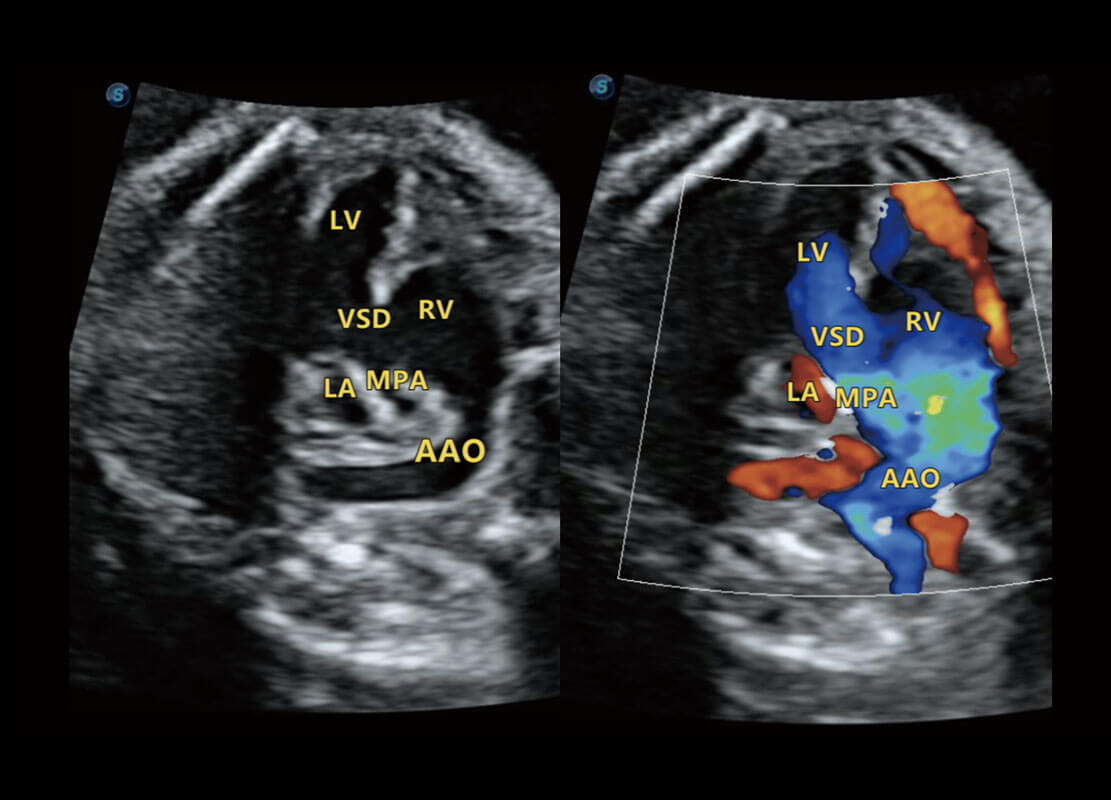

P60搭载一系列胎儿心脏成像技术,实现精细的胎儿心脏评估。

• 四腔切面

• 四腔心血流

• 右室双出口

• 胎心容积成像